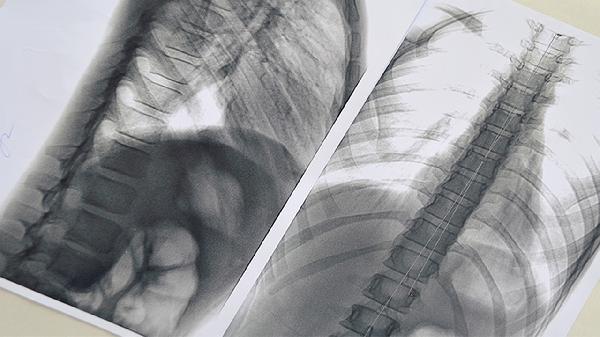

2、影像学检查在阿尔茨海默病的诊断中起着重要作用。脑部MRI可以显示脑萎缩的特定模式,如海马体萎缩,这是阿尔茨海默病的典型表现。CT检查可以排除脑肿瘤、脑出血等其他脑部疾病。功能影像学检查如PET扫描可以检测脑部的代谢活动,观察β淀粉样蛋白的沉积情况,这些信息有助于早期诊断。